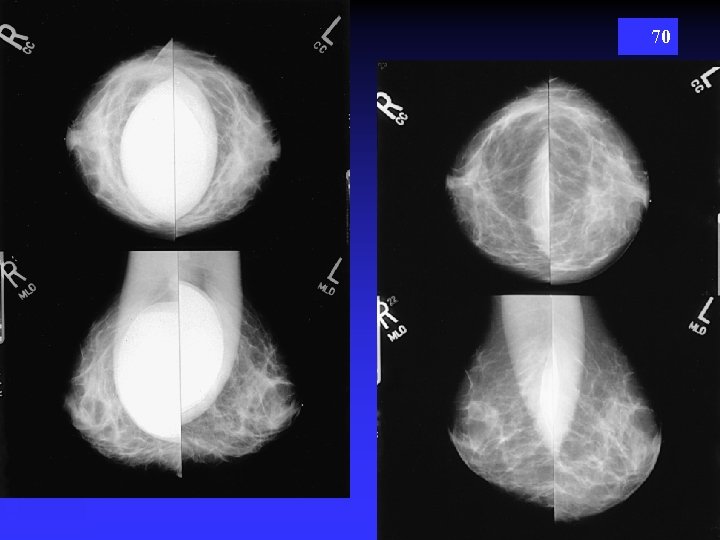

68 “PUSH BACK” TECHNIQUE

69

70